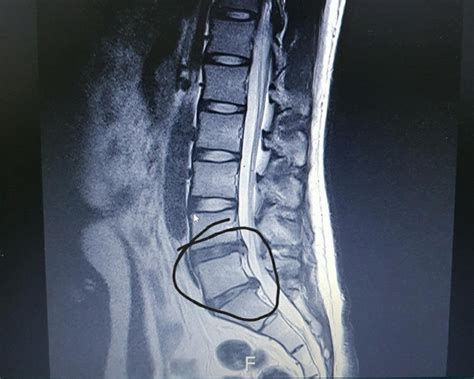

디스크에 과도한 힘이 가해지거나 노화 등으로 인해 섬유륜이 손상되면, 내부의 수핵이 밖으로 튀어나올 수 있습니다. 이때 튀어나온 수핵이 신경을 압박하여 통증이나 감각 이상, 심하면 마비 증상까지 유발할 수 있는데, 이를 흔히 **허리디스크(요추 추간판 탈출증)**라고 부릅니다.

디스크가 터지면(추간판 탈출증) 신경이 압박되거나 자극을 받아 다양한 신경통증이 나타납니다. 대표적인 증상과 통증 양상은 다음과 같습니다.

**디스크 돌출(추간판 탈출증)**은 척추 사이의 디스크가 돌출되어 신경을 압박하거나 자극하는 상태입니다. 이로 인해 일상생활에 다양한 불편과 제한이 발생할 수 있습니다.

나이가 들수록 디스크(추간판) 문제가 더 흔해지는 주요 원인은 노화로 인한 디스크의 구조적 변화와 기능 저하입니다.

디스크는 젊을 때 약 70~80%가 수분으로 구성되어 있어 충격을 흡수하고 척추뼈 사이의 쿠션 역할을 합니다. 그러나 나이가 들수록 디스크의 수분 함량과 탄력성이 점차 줄어들어, 쉽게 마모되고 찢어지며, 높이도 감소합니다. 이로 인해 신경이 압박될 위험이 커지고, 추간판 탈출증(허리디스크, 목디스크) 등 문제가 더 쉽게 발생합니다. - 디스크 노화 및 퇴행성 변화: